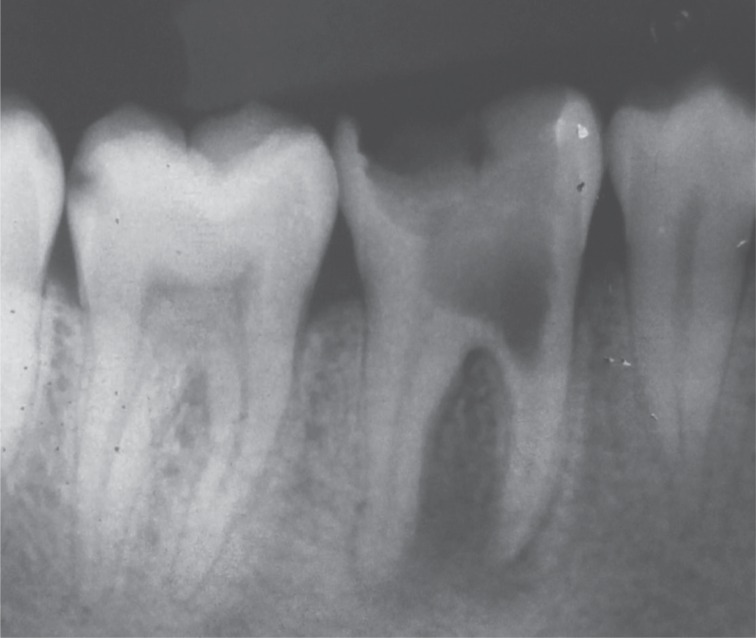

9). The patient returned for follow-up after 6, 12, and 20 months, and the radiographs revealed appreciable healing in the periapical area (

Figures 10,

11,

12,

13).

Figure 10Six month follow-up radiograph.

Figure 11One year follow-up radiograph showing appreciable healing in the periapical area.

Figure 12Twenty month follow-up radiograph.